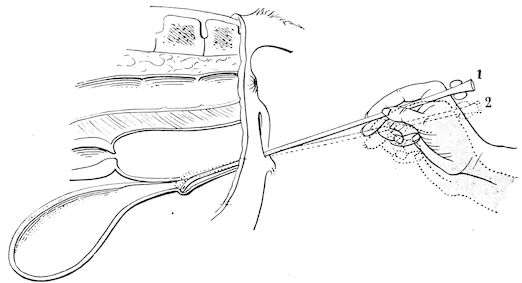

| Œsophagus | 734 | |||

| Passing the probang | 735 | |||

| Crushing foreign bodies in the œsophagus | 735 | |||

| Œsophagotomy | 736 | |||

| Sub-mucous dissection of the foreign body | 736 | |||